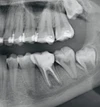

Diş Çürükleri

Diş Eksikliği

Diş ve Diş eti hastalıkları